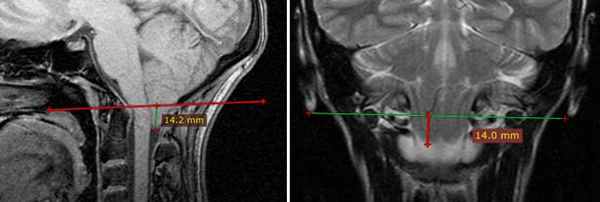

При МРТ - исследовании четко визуализируется положение зубовидного отростка, состояние мягкотканых структур, степень паннуса, последствия подвывиха или вывиха (состояние спинного и продолговатого мозга, окружающих мягких тканей).